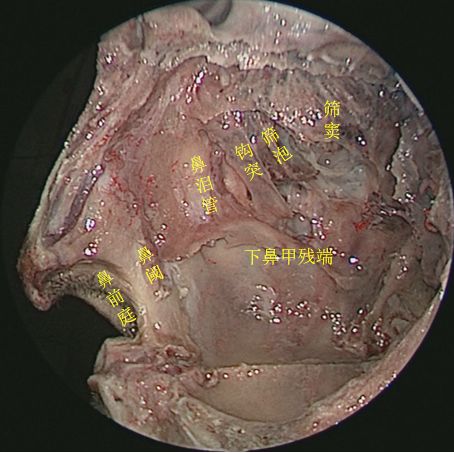

切除中鼻甲后观察鼻腔内整体空间形态

侧方观察右侧鼻腔侧壁结构

45度角观察右侧鼻腔侧壁

切除右侧中鼻甲后观察右鼻腔侧壁

切除中、下鼻甲后抵近观察右侧鼻腔侧壁